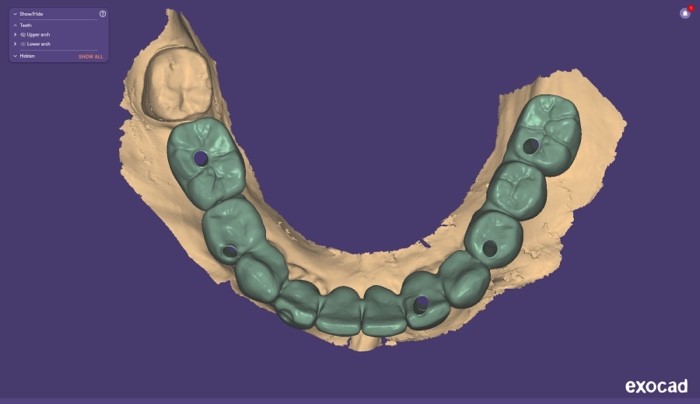

Si procedeva quindi alla scansione degli iPhysio® utilizzando uno scanner intraorale (IS 3600®, Dexis, Envista Holding Corporation, Brea, USA) (Fig. 4 a). Inviavamo i file STL al laboratorio odontotecnico per progettare e realizzare la protesi finale (Fig. 4 b,c,d,e,f).

Progetto CAD finale

Fig. 4(a)

Progetto CAD finale 2

Fig. 4(b)

Progetto CAD finale 3

Fig. 4(c)

Progetto CAD finale 4

Fig. 4(d)

Progetto CAD finale 5

Fig. 4(e)

Progetto CAD finale 6

Fig. 4(f) Progetto CAD finale della protesi.